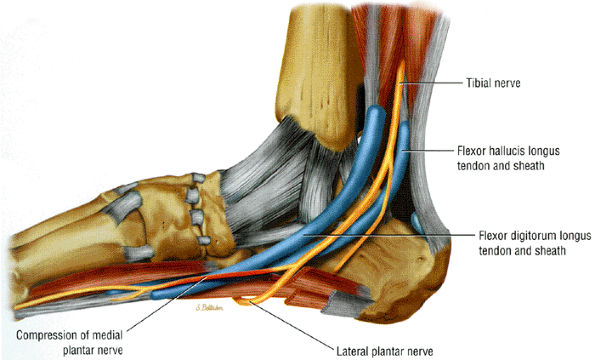

FIGURE 6.51 ● Compression of the medial plantar nerve at the knot of Henry.

-

Deep to or by the fascial edge of a hypertrophied abductor hallucis muscle

At the medial edge of the quadratus plantae muscle, where the nerve changes from a vertical to a horizontal course

Tenosynovitis with tendon sheath distention at the intersection of the flexor digitorum longus and flexor hallucis longus tendons in the talonavicular region may occur in entrapment of the medial plantar nerve.

Muscle denervation edema or atrophy of the abductor hallucis and flexor digitorum brevis muscles, seen on MR images of the ankle, is compatible with medial plantar nerve entrapment (Fig. 6.52).